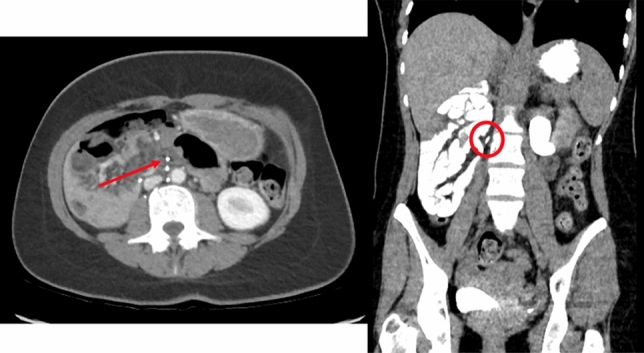

Introduction: Trocar insertion is an essential part of laparoscopic surgery. Vascular injury and gastrointestinal perforation are the most common access-related complications. Veress needles and placement of primary trocar are most commonly implicated in vascular injuries. Herewith, we present a case of an abdominal wall hematoma resulting from a 5-mm port insertion and review the literature.

Case Report: A 43-yer-old female presented with lower abdominal pain for 2 days associated with nausea and fever. She was diagnosed with acute appendicitis and was taken for laparoscopic appendectomy. Access to the abdomen was achieved using a Veress needle at the left upper quadrant. A supraumbilical midline incision was made and a 10-mm optical trocar was inserted into the abdomen. Subsequently, two 5-mm bladed trocars were inserted in the left lower quadrant and suprapubic region. The rest of the procedure was carried out in a routine fashion. Notably, the trocars were removed under direct visualization and with no apparent bleeding from the port sites. A few hours later, a 10 × 15-cm swelling was found over the lateral abdominal wall port site associated with skin ecchymosis. The swelling was asymptomatic and the patient was discharged the next day. She presented to the emergency room 10 days later with pain associated with swelling and fever. CT imaging confirmed an abscess collection associated with the hematoma which was percutaneously drained. The patient was discharged 3 days later after removal of the drain

Discussion: The reported rate of vascular injury is about 1 to 6 per 1000 laparoscopic surgeries. Abdominal wall vessels, most commonly the inferior epigastric artery, or intraabdominal mesenteric or larger vessels may be injured. Bleeding is rarely observed during surgery as the insufflated abdomen creates a tamponade effect over the vessel. A hematoma, as seen in our case, develops in the recovery room or up to 2–3 days postoperatively. Bladed cutting trocars are more likely to cause vascular injury than smooth trocars. Abdominal wall hematomas may be managed conservatively unless causing hemodynamic instability. Mortality associated with intraabdominal injury is about 15%. Knowledge of the abdominal wall anatomy, transilluminating the abdominal wall before introducing trocars, and entering the abdomen at the correct angle decrease the possibility of vascular injury.

Figure Rule of 2/3rd. Medial 2/3rd of the abdominal wall is unsafe for trocar insertion except of avascular midline.